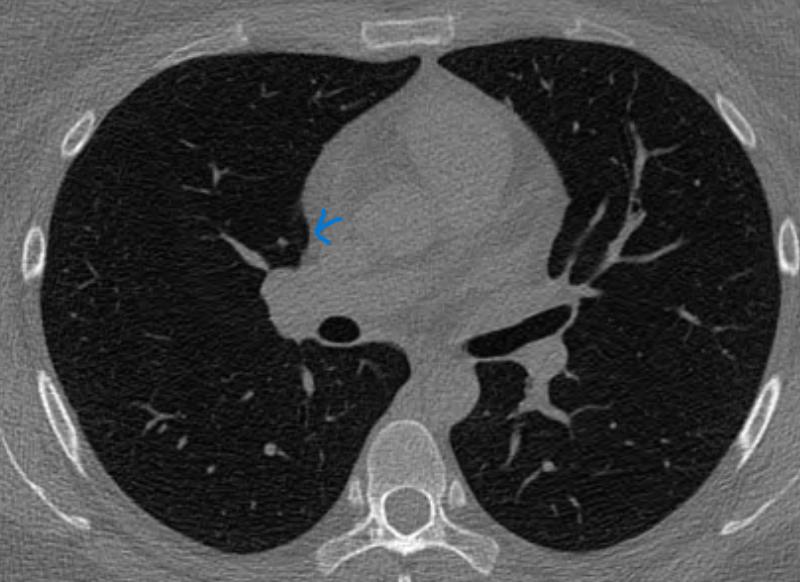

*좀더 하얀색인 사진 2장은 24년 조영제 폐CT 이고, 나머지 3장은 25년 저선량 CT사진입니다.

♧ 고형 같나요 간유리 같나요?

Ai 는 우상엽 solid라는데 오늘 2차병원에서 중간위치고 간유리에 가깝다라고 들어서요

solid nodule인지 ground glass nodule인지는 clear cut하게 나누어지는 것이 아닙니다. 결절이 색이 또렷하면 solid nodule인 것이고 흐지부지하면 ground glass nodule인 것입니다. 이건 육안 소견을 두고 말하는 것입니다. 따라서 일부 nodule에 있어서는 판독하는 의사에 따라 소견이 다를 수 있습니다.